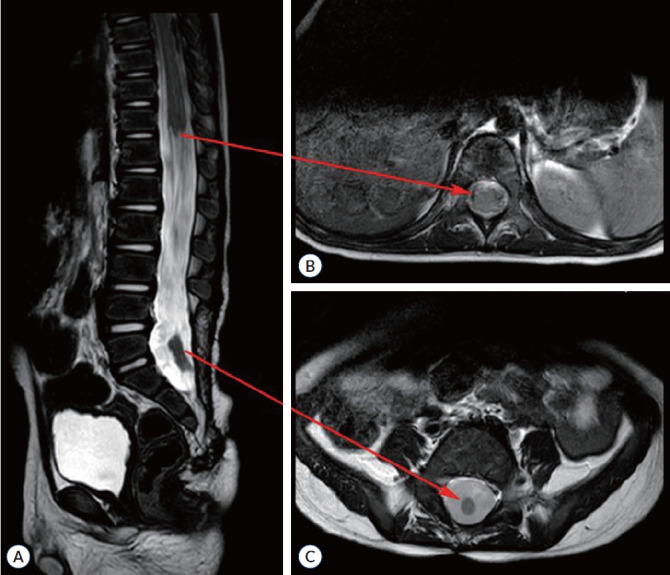

Abstract Image